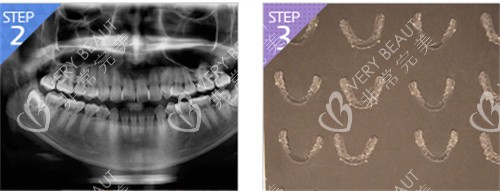

特色三:韓國(guó)必嫵先做雙鄂后做正畸效率翻倍

對(duì)于國(guó)內(nèi)的雙顎手術(shù)來(lái)說(shuō),是往往先正畸后正頜。

在韓國(guó)這邊為了縮短時(shí)間往往是先做手術(shù),在恢復(fù)的過(guò)程中就開(kāi)始戴牙套進(jìn)行固定。

當(dāng)然韓國(guó)必嫵這里也有專門的牙科科室,在設(shè)計(jì)好手術(shù)后,口腔院長(zhǎng)就會(huì)把您的牙套制定出來(lái),這樣一邊在恢復(fù)一邊戴牙套,事半而功倍。